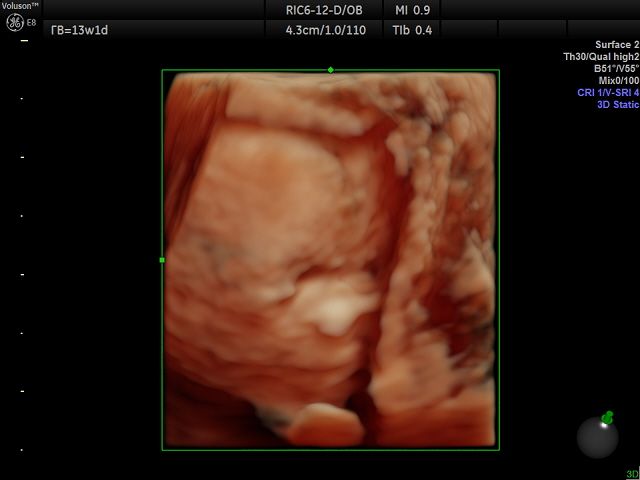

ну в принципе на человечка уже похож!!))) отчетливо было видно пальчики на руках и ушки! глазки ещё закрыты! кожа совсем тоненькая ! )) мне было интересно разглядывать со всех сторон!)) он как маленький инопланетяшка))) сходи обязательно! не пожалеешь! масса эмоций!)))

вот так личико выглядит в 13 недель!))